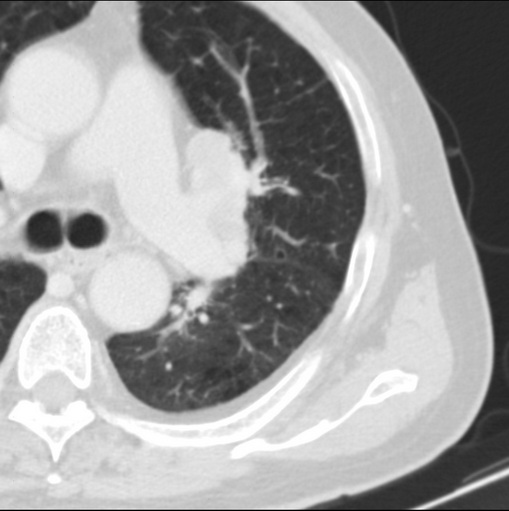

男性患者 81岁 咳嗽 咳痰 咯血

肿块贴近左肺门,包绕左上肺动脉,形态不规则。肿块增强扫描中度强化。纵膈内主动脉弓左旁间隙、气管隆突前、下间隙见多枚淋巴结影。综上考虑左侧中央型肺癌可能性大。图片没有完整上传,尤其是左肺上叶支气管分支层面没有上传,因此不好判断是叶支气管中断还是段支气管中断。另外,下图红色部分所示是“黏液支气管征”吗?